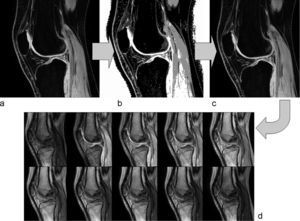

En las imágenes de la primera secuencia eco de gradiente se seleccionó el cartílago mediante una segmentación parcialmente automática basada en la umbralización por intensidades para minimizar la variabilidad debida al usuario17. Tras separar el cartílago se realizaron ajustes por correcciones manuales en aquellos casos en que el método no separó automáticamente el cartílago patelar del femoral. Una vez realizada la segmentación completa del cartílago patelar, esta se utilizó como máscara para el cálculo del T1. Dado que las imágenes para el cálculo de T1 presentaban una menor resolución espacial, fue necesario realizar una interpolación bicúbica para asegurar la coherencia espacial. En la figura 1 se puede ver un ejemplo de segmentación del cartílago patelar mediante esta metodología.

donde S(α, x, y) es la señal para un píxel situado en las coordenadas (x, y), M0(x, y) corresponde a la magnetización en equilibrio térmico y T1(x, y) es el valor de T1 nativo que se desea calcular. De esta expresión se conocen los valores de S para los distintos píxeles y valores del ángulo de inclinación y TR, que no varía a lo largo de la secuencia. Por tanto es posible calcular para cada píxel del cartílago los valores de M0 y T1. Para ello se utilizó un método de ajuste de curvas por mínimos cuadrados18. De esta forma, al generar una curva ajustada a la variación de la señal con el ángulo de inclinación, se obtuvo directamente el valor de T1 de cada píxel (fig. 2). Tras realizar el ajuste para cada píxel se genera de forma automática un mapa paramétrico en color que muestra las variaciones regionales de los valores de T1 para el cartílago patelar.Las medidas de T1 se realizaron para todo el cartílago (T1 promediado global) y también para aquellas áreas etiquetadas como normales, degeneración inicial o avanzada según los criterios modificados de Outerbridge para RM (T1 específico por áreas). Estas áreas específicas se seleccionaron manualmente por un radiólogo experimentado sobre el cartílago previamente segmentado. Todo el análisis de las imágenes se realizó mediante una herramienta informática de cuantificación propia.

DiscusiónEn este estudio se ha demostrado la utilidad del cálculo del tiempo de relajación longitudinal T1 como biomarcador de imagen por RM para evaluar diferencias entre los distintos grados de degeneración del cartílago patelar. Los mapas paramétricos de T1 permiten visualizar la distribución regional de las anomalías (fig. 4) y realizar medidas objetivas mediante regiones de interés sobre las áreas más afectas. La utilidad es mayor cuando se analizan regionalmente los datos de T1 del cartílago.

La representación de los mapas de T1 como imágenes paramétricas coloreadas (fig. 4) permite estudiar el cartílago de manera regional y realizar una caracterización mucho más exacta y localizada de la degeneración. En este estudio ha quedado demostrado que la utilización de los estadísticos tradicionales (media y desviación típica) no es adecuada para caracterizar el cartílago a nivel global. En estos casos el efecto de la media enmascara cualquier variación en los valores que indique algún grado mayor de degeneración del cartílago. Se sugiere por tanto la utilización de estos mapas paramétricos, que permiten evaluar el cartílago a nivel global y localizar posibles áreas de afectación severa de una forma rápida.